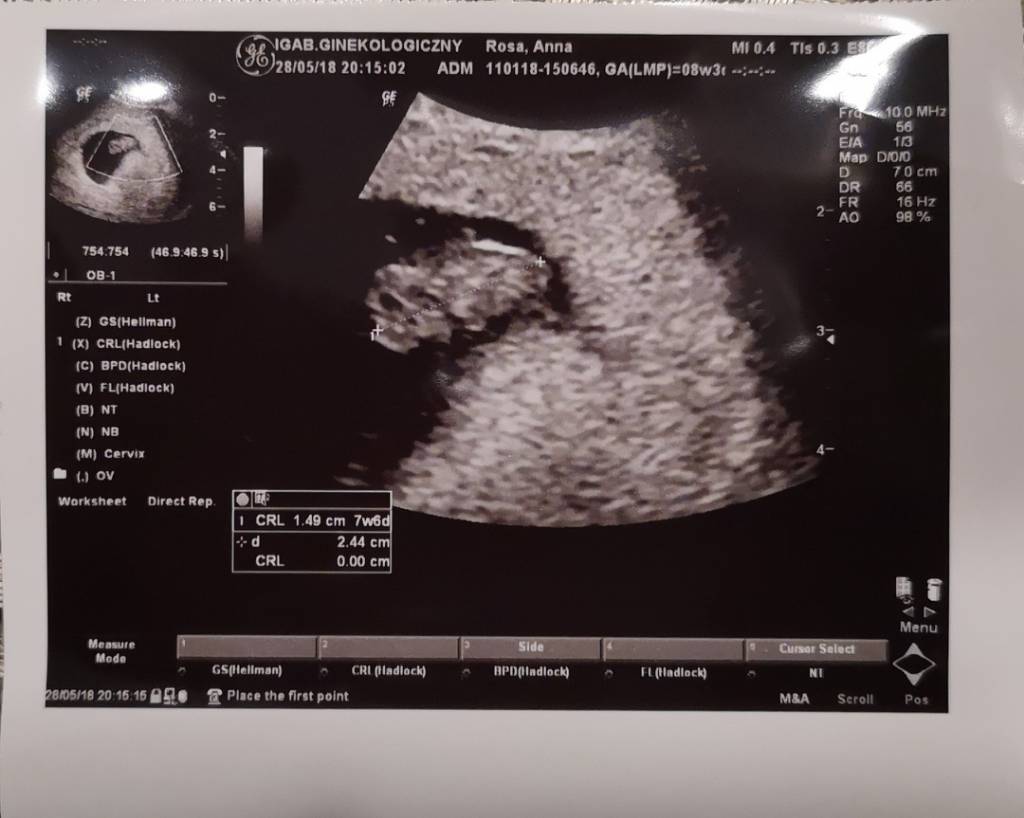

Jeśli chodzi o mój tydz ciąży ta na każdym suwaczku inaczej ale może uda mi się wkleić. Ale prawidłowy to chyba 8 tydz 2 dni